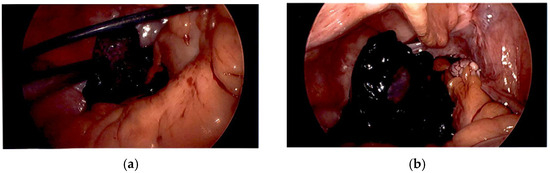

Case Summary